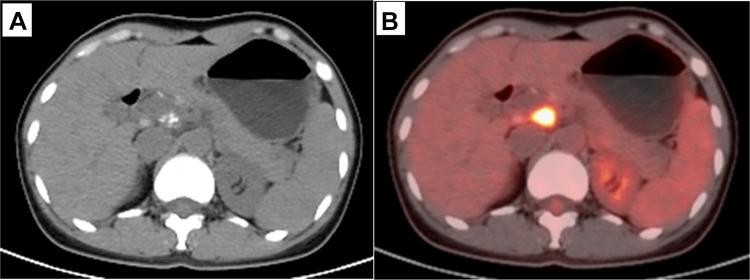

The special location of abdominal tuberculosis makes it difficult for biopsy, while its clinical and imaging characteristics make it indistinguishable from tumors. Here, we report a female patient that was initially misdiagnosed with pancreatic cancer, but eventually correctly diagnosed with tuberculosis in the celiac lymph nodes using F-FDG PET-CT. She was 38 years old. Her main complaint was "deep abdominal pain and discomfort for nearly a month", accompanied by nausea and vomiting. Diagnosis of pancreatic tumors or enlarged lymph nodes was initially made based on CT scan results. Abdominal MRI revealed enlarged lymph nodes. F-FDG PET-CT imaging revealed a soft-tissue mass about 2.8 cm in diameter in the hepatic hilar area with a maximum standardized uptake value (SUV) of 9.4, and delayed imaging measured the SUV at 12. Enhanced CT showed no vascular envelopment in the mass. Based on these results, the patient was diagnosed with tuberculosis in the celiac lymph nodes. Her tuberculin test was strongly positive. After 5 months of antituberculosis treatment, the mass had reduced to about 1.5 cm in diameter and SUV reduced to 8.1, as demonstrated by F-FDG PET-CT imaging. Abdominal lymph-node tuberculosis is easy to misdiagnose, but timely F-FDG PET-CT imaging combined with tuberculin testing may reduce misdiagnosis and mistreatment.